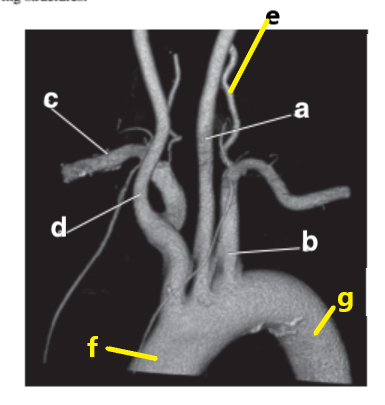

What is letter e?

Subclavian artery

What is letter f?

Vertebral artery

What is letter c?

Aortic arch

Which letter is the left common carotid?

a

Abdominal aorta

Which letter is the Right vertebral artery?

f

Ascending aorta

Descending aorta

Carotid bifurcation